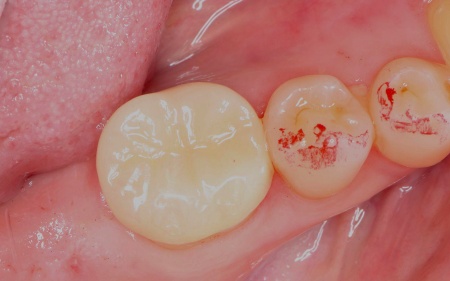

オンレーは、歯全体を覆う被せ物と比べると歯を削る量を抑えられるため、健康な歯をできるだけ残しながら、歯の強度を高めることが可能です。ただし、歯の状態によっては適応できない場合もあります。 まず、すでに装着されていた金属の詰め物を除去し、歯の状態を慎重に確認します。 次に、採取した歯型をもとにオンレーを作製します。 最後に、完成したオンレーを専用の接着剤で装着し、見た目や噛み合わせに問題がないことを確認して、治療を終了しました。 患者様の上の歯の治療についてはこちら:https://dr-kaiya.com/blog/20260312-1/ |

治療中

治療後